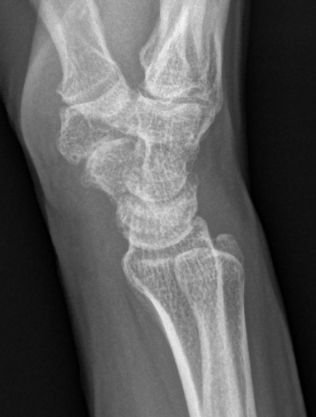

Lateral xray

Distal radius / lunate / capitate: not aligned, spilled teacup

Normal versus spilled tea cup appearance on lateral with spilled tea cup